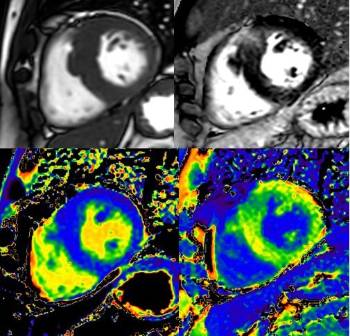

De acuerdo a la cardióloga del Hospital la Luz, gracias a esta tecnología, no sólo somos capaces de analizar de forma macroscópica el funcionamiento y anatomía del corazón, sino que también somos capaces de caracterizar y estudiar las propiedades del miocardio, mediante técnicas de mapeo que aportan una cuantificación directa y objetiva del miocardio, permitiendo detectar anomalías que son demasiado sutiles para identificarlas en un examen visual.

"También es posible valorar los flujos valvulares y la presencia de cortocircuitos de una forma novedosa y más precisa mediante el uso de secuencias como el 4D-Flow (herramienta de diagnóstico cardíaco), así como la valoración anatómica de la aorta y grandes vasos sin la necesidad de utilizar contraste, siendo esto último de gran utilidad en pacientes con contraindicación para ello", indica la doctora Romero Daza.